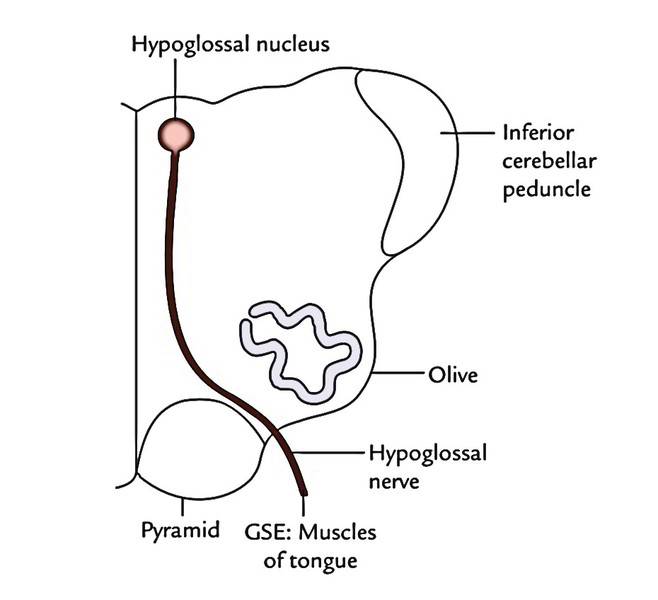

Motor Cranial Nerves – Anatomy, Functions & Components | Kenhub

Hypoglossal nerve-Functional component-Nucleus-Course-Distribution …

Motor cranial nerves: Anatomy, functions and components | Kenhub

Hypoglossal Nerve Intermedullary Course

Hypoglossal Nerve Intermedullary Course